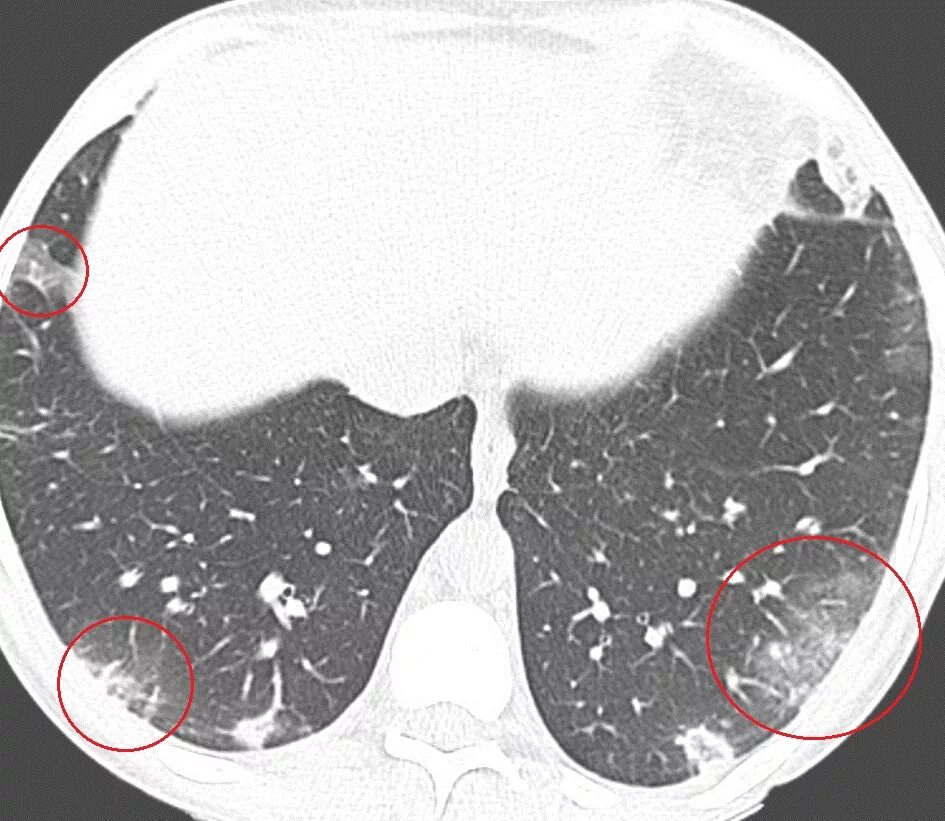

Уплотнения паренхимы по типу матового стекла